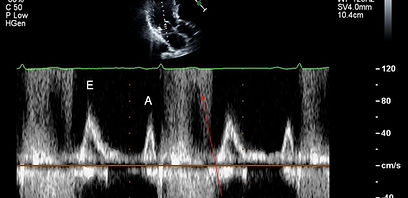

This section covers high-yield concepts to help you appreciate the principles behind how the echo machine transforms the information it receives from the transducer into the images we see displayed. Knowledge of these principles will also help you to troubleshoot situations when the information displayed is incompatible with physiologic or expected values, or when artifacts are suspected. Click here if you want to test your knowledge of echo physics. You will find 50 MCQs with explanations.